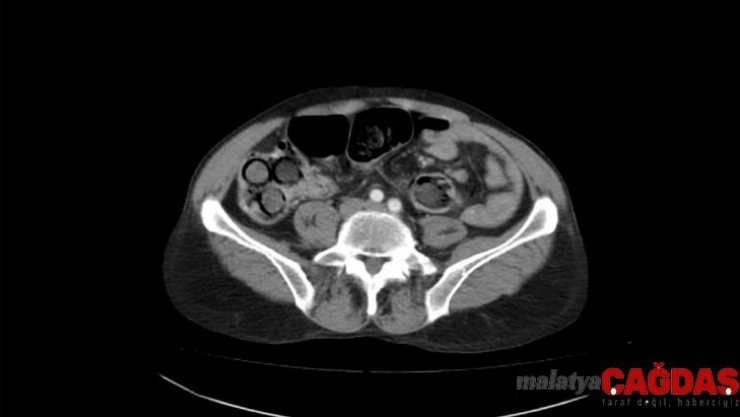

Polis, şahsın midesinde eroin olabileceğinden şüphelenip hemen hastanenin gastroenteroloji bölümüne götürdü. Burada tomografisi çekilen midede, sosis büyüklüğünde paketler tespit edildi. Ancak polis, emin olmak için daha sonra şahsa endoskopi işlemi de yaptırdı. Bu sayede ucunda ışıklı küçük bir kamera bulunan ve endoskopi adı verilen bir cihaz yardımıyla şahsın yemek borusu, mide, onikiparmak bağırsağı ve kalın bağırsaklarında 49 paket sosis büyüklüğünde paketler olduğu kesinleşti.